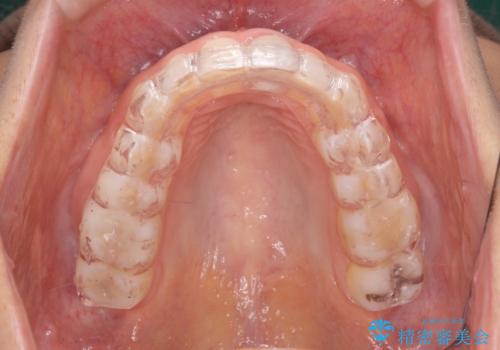

夜中の歯ぎしり ナイトガードで予防

- 20代女性

- 1ヶ月

- 2-5回

- 夜中の歯ぎしりをどうにかしたいとのことで来院されました。

ナイトガードを作成し歯ぎしりによる歯のすり減りを予防していきます。

- ナイトガード 33,000円費用は治療当時の料金となります

患者様ごとのナイトガードをオーダーメイドで作ることで、適合がよく咬合圧も分散させることができるようになります。